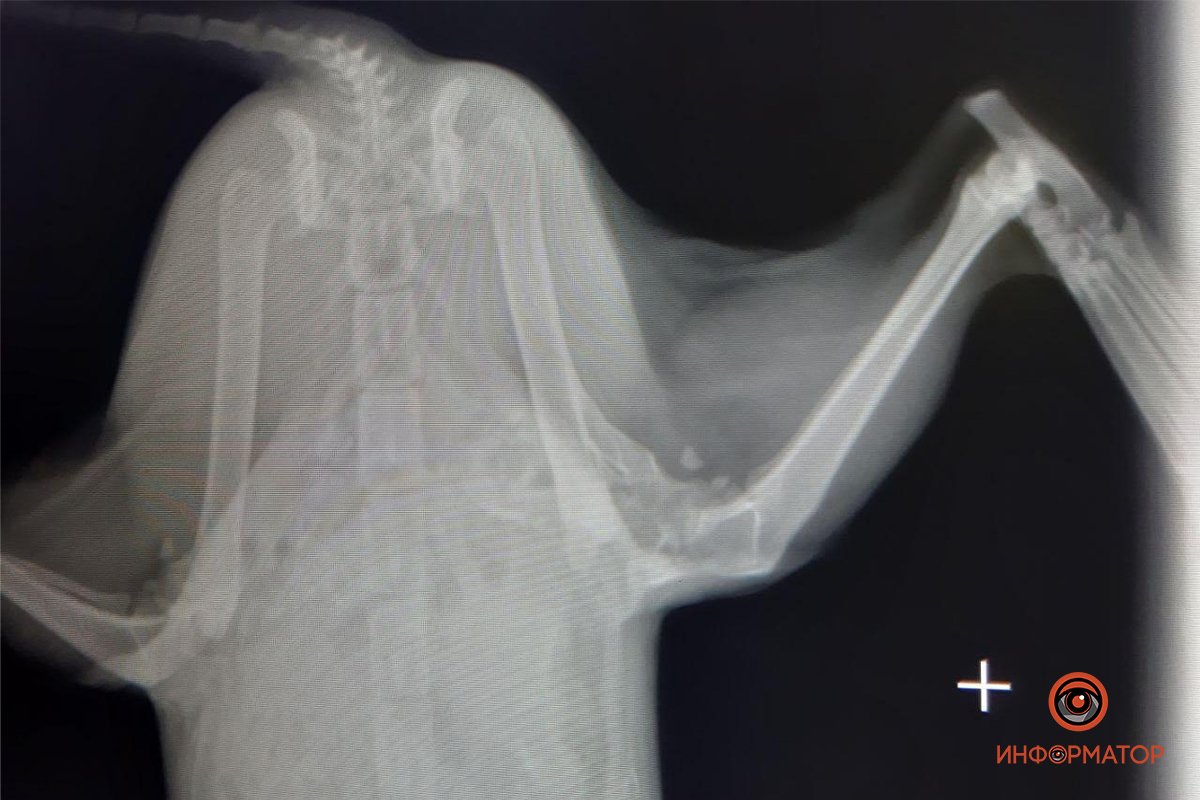

Человеческая жестокость не знает пределов. В Днепре волонтеры фонда «Мы за право на жизнь» спасают породистую кошку, которую выкинули из дома. Предварительно, Снежка попала под машину, либо кто-то ее сильно ударил. У кошки тяжелый перелом лапы.

Также у нее гнойные выделения с кровью – это показатель гнойной пиометры матки. Об этом сообщает Информатор, ссылаясь на публикацию Ольги Уманчик.

Снежка обезвожена, ее тошнило, после чего она перестала есть. Животное сейчас находится под капельницей и нуждается в срочной операции. На данный момент на лечение кошки волонтеры потратили более 1,5 тысяч гривен. На операцию, даже по скидке, требуется еще от 3,5 до 4,5 тысяч. Также необходимо будет оплатить минимум 3 недели стационара.